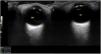

The ocular ultrasound examination is performed with the patient in the supine decubitus position with the eyes closed. At least 2 sagittal views should be obtained with the probe perpendicular to the horizontal meridian to visualize the globe and optic nerve (Sag). It is also useful to perform a transverse scan (Tran) to visualize the iris and pupil and assess the pupillary light reflex. A high-frequency (5–10MHz) linear probe is placed on the upper eyelid in the coronal plane at the level of the crystalline lens to visualize the iris, a structure surrounding an anechoic circular area that corresponds to the pupil. The images on top show both eyes in miosis upon the shining of a light through the eyelids. The “as low as reasonably achievable” (ALARA) approach must be applied to minimise thermal and mechanical indices. OD, right eye; OS, left eye.